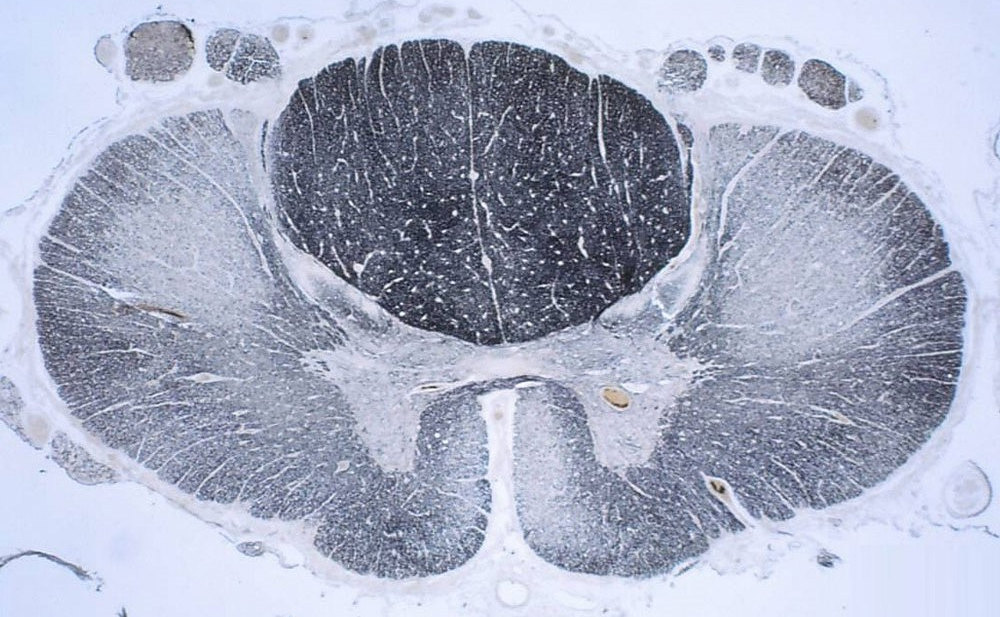

A human cervical spinal cord slice. Once you’ve read this post, you should be able to identify the major parts and tell which side is the front of the cord.

Welcome to day thirty-three in our series. For those of you who are just finding us, we have every one of these posts in our neuroanatomy category in reverse chronological order. Today we’re going to backtract (get it?) a little and go over something basic, but something we’ve skipped over to this point. We never really talked about the landmarks of a spinal cord slice. So today, we are going to take a detour and go over spinal cord features.